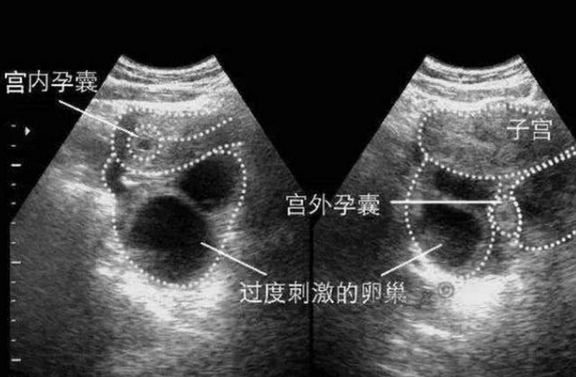

3、超聲檢查:確定妊娠部位及胚胎是否存活;